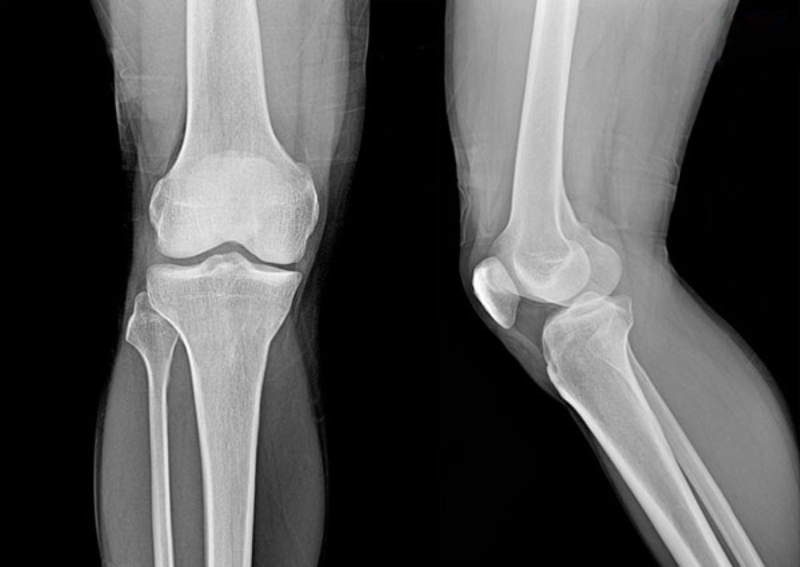

Quá trình chẩn đoán trật khớp không phức tạp và mất nhiều thời gian như một số bệnh xương khớp mạn tính khác. Sau khi kiểm tra cử động khớp, hình dạng khớp và sự thay đổi màu sắc da xung quanh khớp bị chấn thương, bác sĩ sẽ tiến hành chụp phim X-quang.

Hình ảnh chụp X-quang cho thấy rõ đầu xương có bị bong hoặc lệch khỏi ổ khớp hay không, giúp kết luận trật khớp chính xác

Hình ảnh X-quang cho thấy rõ tình trạng các đầu xương và ổ khớp giúp bác sĩ kết luận chính xác bạn có bị trật khớp hay không? Ngoài ra, bác sĩ có thể thực hiện thêm xét nghiệm cộng hưởng từ MRI để đánh giá cụ thể mức độ tổn thương của các cấu trúc mô mềm xung quanh khớp bị trật gồm dây chằng, mạch máu, gân và dây thần kinh, từ đó xác nhận chi tiết những gì đang xảy ra ở khớp.